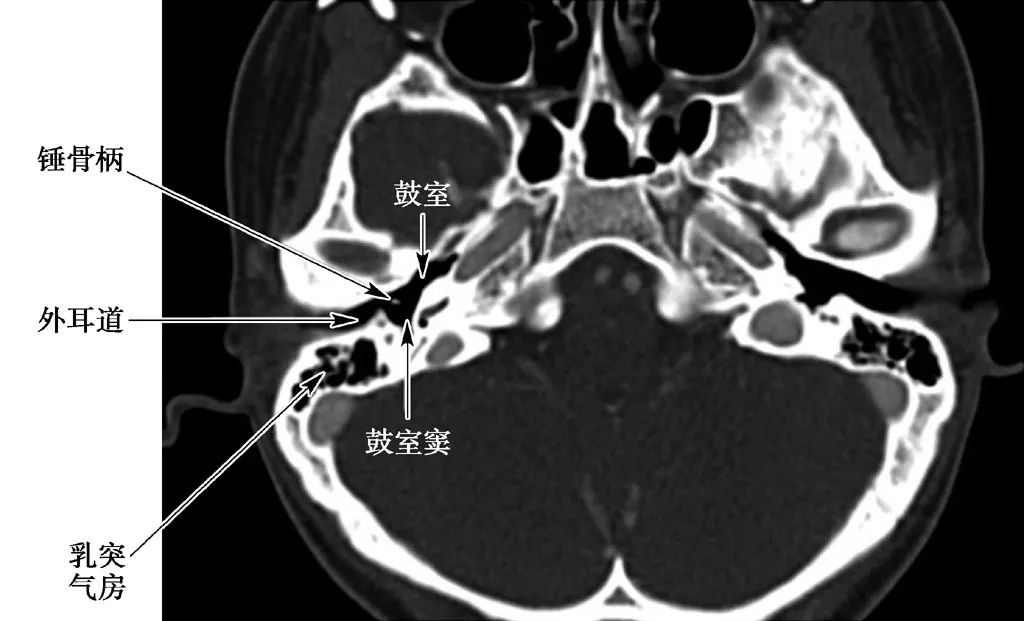

外耳道结构

(CT横断面)

包括鼓室、咽鼓管、乳突窦和乳突小房。

1.鼓室

鼓室为位于颞骨岩部的不规则含气腔隙。

鼓室内含3块听小骨——锤骨、砧骨、镫骨。

3.乳突窦

乳突窦向前经乳突入口与上鼓室相通,向后与乳突小房相通,中耳病变可经乳突窦侵入乳突小房。